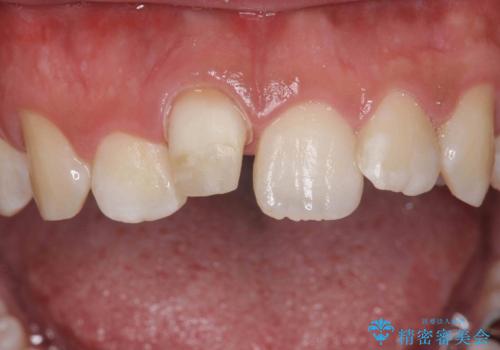

- 前歯の変色を主訴に来院。

神経が死んでいたため、神経の治療を行いました。

- 24.2万円 内訳:セラミッククラウン(ジルコニアクラウン、スペシャル)14.3万円、精密根管治療(前歯、イニシャル)6.6万円、仮歯1.1万円、ファイバーコア2.2万円費用は治療当時の料金となります

神経が死んでしまった歯は時間がたつと変色してきてしまいます、セラミックでかぶせると色を改善することが可能です。